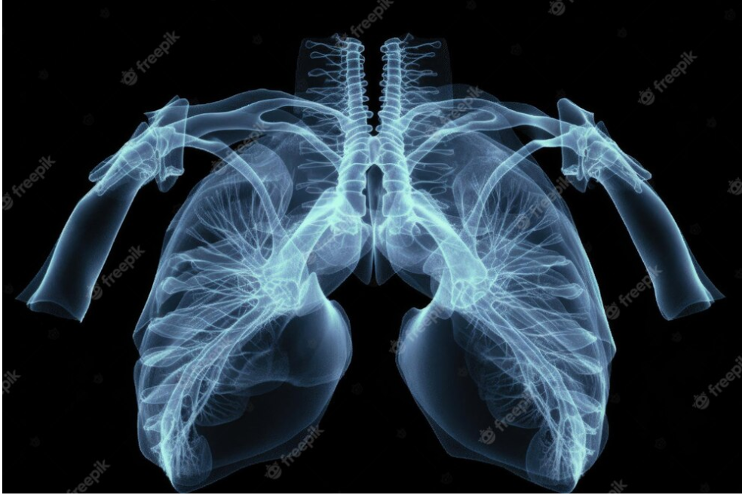

Hình 3: Hiện nay, có hai loại bệnh tim bên phải chính: Tim bên phải và đảo ngược phủ tạng và tim bên phải và không có đảo ngược phủ tạng

Các thể lâm sàng của tim nằm bên phải:

Hiện nay, có hai loại bệnh tim bên phải chính: Tim bên phải kèm theo đảo ngược phủ tạng và tim bên phải nhưng không kèm đảo ngược phủ tạng khác

Tim bên phải và đảo ngược phủ tạng

Loại này xảy ra khi đầu (đỉnh) tim của bạn hướng về phía bên phải của ngực. Các cơ quan khác của người bệnh cũng bị đảo lộn. Điều này ảnh hưởng đến các cơ quan ở ngực và bụng (bụng) như phổi và gan. Đặc biệt, loại bệnh tim này có thể gây ra các triệu chứng, thường liên quan đến đường ruột, thực quản, phế quản và tim, trong đó một số có thể đe dọa tính mạng nếu không được điều trị.

Tim bên phải và không có đảo ngược phủ tạng

Đây là loại bệnh tim bên phải hiếm gặp hơn. Cụ thể, các phủ tạng trong lồng ngực và bụng ở vị trí bình thường trong khi tim và mỏm tim ở bên phải. Đôi cấu trúc tim bình thường nên làm chậm trễ việc phát hiện ra các bất thường này. Tuy nhiên, phần lớn bệnh nhân có bất thường bẩm sinh về cấu trúc tim.